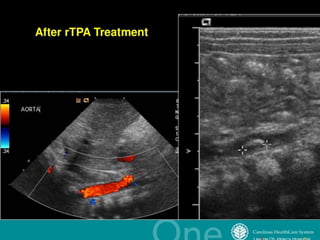

Catheter-related thrombosisCatheter-related thrombosis

Venous thrombosisVenous thrombosis

Arterial thrombosisArterial thrombosis

Non-Catheter-related thrombosisNon-Catheter-related thrombosis

Renal vein thrombosisRenal vein thrombosis

Neonatal strokeNeonatal stroke

An acute ischaemic

limb in a noenate

secondary to a

catheter related

thrombosis.